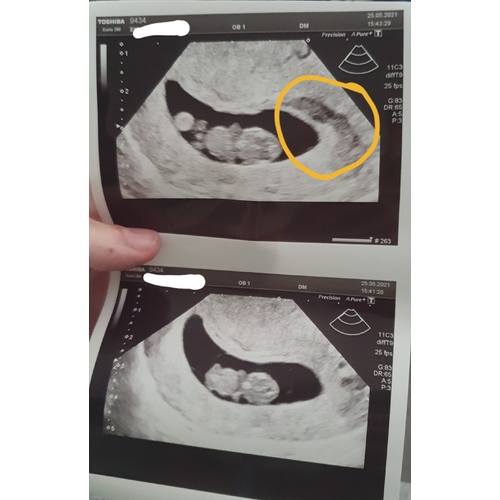

Allereerst, gefeliciteerd met je zwangerschap! Maar wat schrikken zeg! Ik heb ongeveer hetzelfde meegemaakt. Bij +/- 7 weken veel bloed verloren en bij de echo bleek het vruchtje er nog te zijn met een hartslag.

Op de echo was een hematoom zichtbaar.

De echo erna was het vruchtje goed gegroeid, maar was de hematoom nog steeds aanwezig. De hematoom kan zelf oplossen of er nog uitkomen aldus de arts. Een spannende tijd...